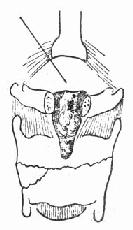

(1)急性声门上损伤:声门上损伤包括甲状软骨板上半部骨折和会厌损伤(图96-1)。有急性喉阻塞者首先行常规气管切开术,然后行前连合直接喉镜检查,注意喉水肿和喉及下咽粘膜裂伤的情况。手术包括缝合粘膜裂口并切除会厌及会厌谿之血肿组织,颈前在舌骨水平做横切口,剪断舌骨后,给行切开甲舌膜进入咽腔(图96-2)。切除会厌,会厌根部血肿组织及双侧假声带(图96-3)。用丝线缝合喉粘膜,尽量对合复位骨折的甲状软骨板,并用丝线缝合甲状软骨外板软骨膜,再缝合甲舌膜(图96-4)。逐层缝合切口。术后48h经鼻咽置入下咽部一条吸引引流管,持续引流。待喉部手术后反应消退,可试行堵管,呼吸道通畅即可拔除气管套管。

图96-3 切除会厌根部血肿